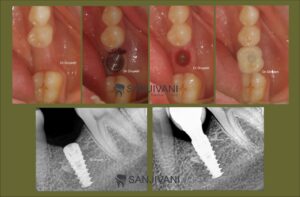

Dental Implants treatment experience in Rajkot

Same-Day Dental Implants in Rajkot

Looking for same-day dental implants in Rajkot?

Our advanced immediate-load implant technology allows placement of implants and fixed teeth in few days, minimizing recovery time and avoiding multiple surgeries.